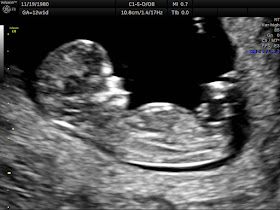

The ten seconds of elation were followed by countless days, weeks, and months of living in fear and anxiety, treading on eggshells with the possibility of something once again going wrong. We didn't talk about "the baby," didn't tell Luc about the arrival of a sibling, and didn't make our usual fanfare of announcements beyond when and to whom it was necessary. I survived from day to day and aimed for that next milestone: the beta blood tests indicating a growing life; the first scan and seeing a yolk sac and fetal pole; hearing that heartbeat; seeing a baby form and the wiggles on ultrasound; getting news after genetic testing that all is checking out well; feeling those first kicks and rolls, so missed and so welcomed.

Mother's Day, 2019. My first baby girl would have turned one year old. I spend the weekend watching my second baby girl squirming on an elective 3D ultrasound, feeling her life inside me, marveling at my luck and my miracle. In the past 7 months since she has been with me, I am torn with trepidation, not daring to believe that this could be true. I hid her from the world as if I could protect her and not jinx her existence. Yet, guilt weighs down on me that I am not fully acknowledging her, accepting her, and opening myself to an unconditional love for her. With pregnancies in close succession, and with the knowledge that it is a girl, I'd often forget and think that I am still carrying Thi. The early onset of morning sickness that lasted into the second trimester, the way in which I would constantly catch colds and coughs, the same cravings I had with girl pregnancies---they all remind me of the baby I carried and lost, and I'd have to snap myself out of a downward spiral of thinking, forcing a reminder that is is a new baby with a different identity and fate, who may not be here, had her older sister lived. I continue to log my basal body temperature. Today is Day 193 of this cycle, and it is a moot point to track temperature this far into a pregnancy, but it serves as a daily reminder not to give up on her. She is the first thing I think about every morning.